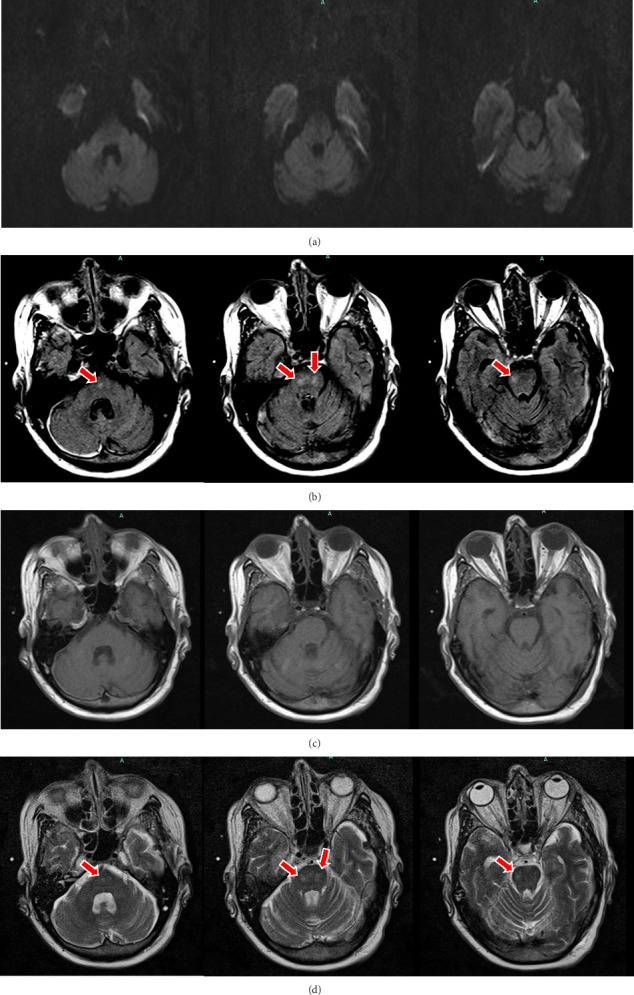

渗透性脱髓鞘综合征(ODS)是一种与钠快速变化有关的罕见并发症,通常发生在严重低钠血症患者身上。而正常血钠患者的脱髓鞘综合征(ODSIN)则较少被提及。我们描述了一名神经创伤后经磁共振成像检测出 ODSIN 的患者,并回顾了相关文献。我们介绍了一名 57 岁女性患者,她在地面摔倒后出现硬膜下血肿。她最初的血钠值为 140 mEq/L,但在两天内上升了 17 mEq/L,最高时达到 157 mEq/L。检查发现,她有无法解释的、意外的左侧偏瘫,面部无力;怀疑是 ODS。磁共振成像显示中央桥脑 T2 高密度、T1 低密度和 FLAIR 高密度。治疗包括用生理盐水和自由水逐步降低钠含量。她出院后住进了一家专业护理机构(SNF),血钠为 138 mEq/L,4 年随访发现她有中度残疾,日常生活需要他人协助。通过文献检索,我们发现了 23 个病例(22 例为正常血钠;1 例由正常血钠发展为高钠血症)。常见体征/症状为反射亢进、构音障碍和步态障碍。常见合并症为酗酒、透析和肾脏疾病/衰竭。头颅磁共振成像证实了所有病例,经常发现中央桥脑T2和FLAIR高密度和T1低密度。我们的综述进一步描述了 ODSIN 的不同病因、临床过程和影像学特征。即使在血钠正常的情况下,当出现神经系统症状时,临床医生也应考虑这一诊断。

Osmotic demyelination syndrome (ODS) is a rare complication associated with rapid sodium changes, typically encountered in patients with severe hyponatremia. ODS in patients with normonatremia (ODSIN) is less recognized. We describe a patient with MRI-detected ODSIN following neurotrauma and reviewed the relevant literature. We present a 57-year-old female with subdural hematoma following ground-level fall. Her initial sodium was 140 mEq/L but over 2 days, rose 17 mEq/L, peaking at 157 mEq/L. On exam, unexplainable, unexpected left-sided hemiplegia with weakness sparing her face were noted; ODS was suspected. MRI revealed central pontine T2 hyperintensity, T1 hypointensity, and FLAIR hyperintensity. Treatment included gradual lowering of sodium with normal saline and free water. She was discharged to a skilled nursing facility (SNF) with sodium 138 mEq/L and upon 4-year follow-up had moderate disability and required some assistance to support activities of daily living. Our literature search yielded 23 cases (22 normonatremic; 1 where normonatremia progressed to hypernatremia). Common signs/symptoms were hyperreflexia, dysarthria, and gait disturbance. Common comorbidities were alcoholism, dialysis, and renal disease/failure. Cranial MRI confirmed all cases, frequently revealing central pontine T2 and FLAIR hyperintensity and T1 hypointensity. Our review further characterizes the diverse etiologies, clinical course, and radiographic features of ODSIN. Clinicians should consider this diagnosis when neurological symptoms occur even in the setting of normonatremia.